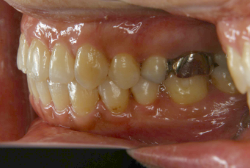

「左奥歯でものが噛めない」という主訴で来院したケースです。診断の結果、基本的には「叢生」という隙間が足りないと言うことが原因の凸凹症例でしたが、左下の乳歯が高校生になってもまだ残存している状態で、そのせいで噛み合わせが極端に悪くなっていました。

検査の結果、乳歯の下には後継ぎの永久歯が先天的に欠如していました。配列の凸凹が厳しく非抜歯で矯正することは難しく、仮に無理をして非抜歯治療をしても後々「後戻り」が懸念されることから、このような症例の場合は通常、上下顎左右第一小臼歯を抜歯させていただくのですが、左下は乳歯を抜歯して、第一小臼歯は残すことにしました。これで結果として、小臼歯部を上下左右で一つずつ減らしたのと同じ状況になります。治療後は歯並びが綺麗になっただけでなく、噛み合わせ的にも正しい状態が確立しています。

このように、先天的に永久歯が足りないという症例は最近増えています。親知らずはなくても特に問題になりませんが、その他の歯が足りないと言うのは審美的にも機能的にも重大な障害となります。しかし、矯正治療を正しく行えば、結果として歯がすべてあった場合と全く同じ仕上げにすることも可能です。